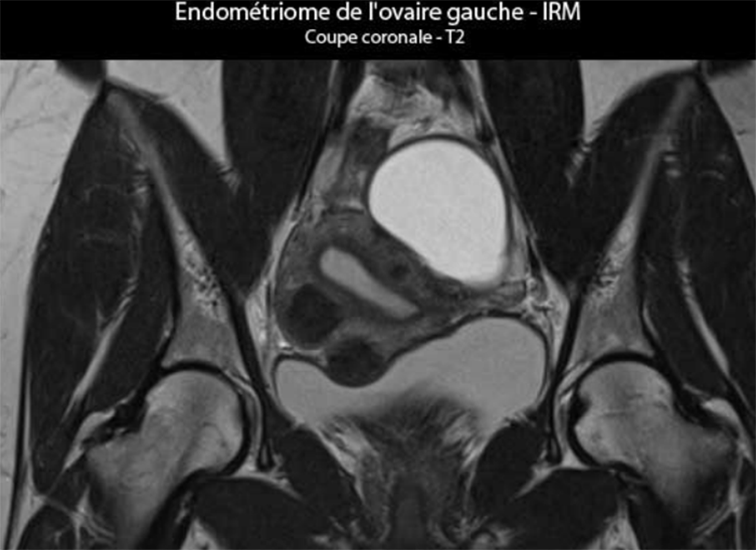

| L'ovaire gauche : images échographiques d'un volumineux kyste endométriosique (84 x 62 x 60 mm uniloculaire, sans végétations endophytiques ni épanchement péritonéal). Le contenu du kyste qui fut observé au cours de la kystectomie n'est pas le liquide chocolaté épais classique des endométriomes, car il s'agissait d'un liquide très fluide brunâtre ferreux. Voir les aspects observés par échographie pour ce kyste |

L'examen anatomopathologique confirme le diagnostic du kyste endométriosique : Il s'agit d'un kyste uniloculaire à paroi lisse tant dans la zone externe que dans la zone interne ; son revêtement interne est très largement abrasé avec d'exceptionnelles cellules d'allure endométriale partiellement détachées, régulières. Il n'est pas retrouvé d'infiltration tumorale. La paroi apparaît légèrement hémorragique avec des rares glandes endométriales cernées par leur chorion cytogène visible. Aspect histologique en faveur d'un kyste de type endométriosique hémorragique sans aucun caractère suspect de malignité retrouvé. Le dosage plasmatique des marqueurs tumoraux montre une élévation du taux de CA 125 : 130 UI/ml pour un taux normal < 24,8 UI/ml. |